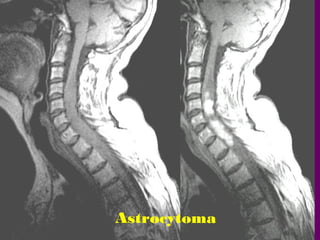

U TEÁ BAØO SAO

(ASTROCYTOMA)

a.Tæ leä : 20-30% u tuyû soáng.

b.Tuoåi vaø giôùi : thöôøng ôû treû

em.

c.Vò trí : Vuøng coå, ngöïc

d.MRI :

Gioáng ependymoma. Coù taïo

keùn,

chaûy maùu; thöôøng taêng

tín hieäu

sau tieâm Gd.

Astrocytoma